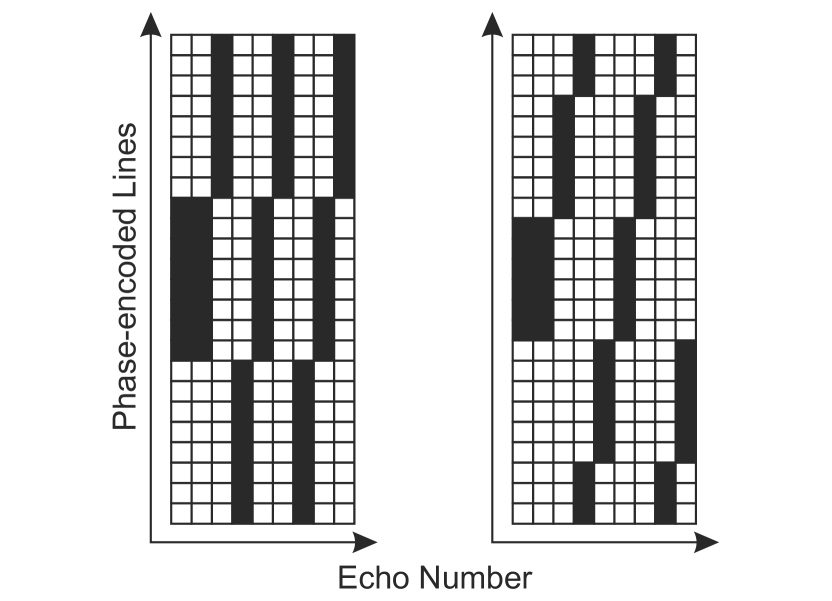

Apart from conventional mono-exponential fitting of echo-time images, simulated and measured SE and MSE data were analyzed using the proposed model-based reconstruction with the GF model (GF-MARTINI = Model-based Accelerated Relaxometry by Iterative Nonlinear Inversion). Undersampling for acceleration factors R of up to was simulated using a ”block” pattern as depicted in Fig. 2.

In contrast to the scheme used for mono-exponential MARTINI [4], the pattern was designed such that the first two echo times are sampled around the k-spacecenter. In combination with the GF model, this strategy was found to minimize deviations in the T2 estimation at different undersampling factors.